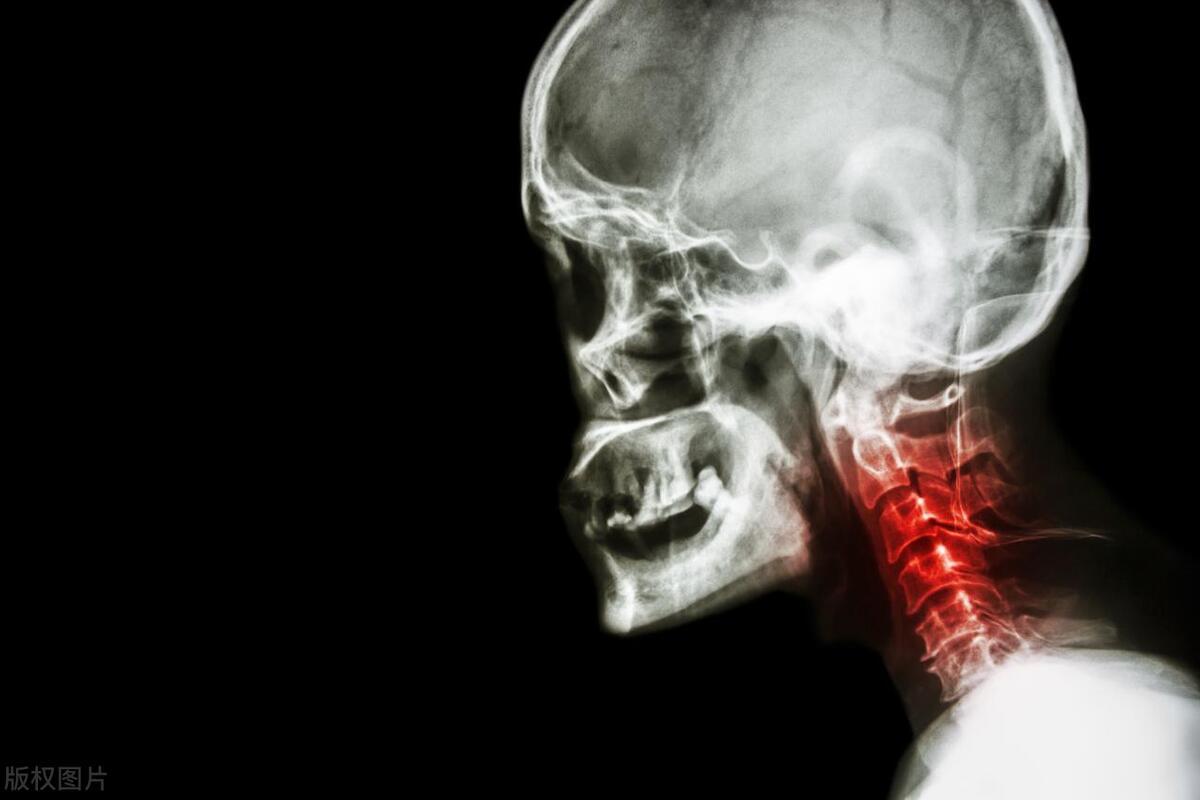

3.影響頸椎健康

河北醫科大學第三醫院骨科主任醫師吳濤表示,在頸椎病的誘因中,使用手機是非常主要的一種致病因素。因爲經常使用手機,需要長時間的低着頭,低頭之後就會導致頸椎間盤所受的壓力增加,使椎間盤壓迫神經,從而引起頸椎病。